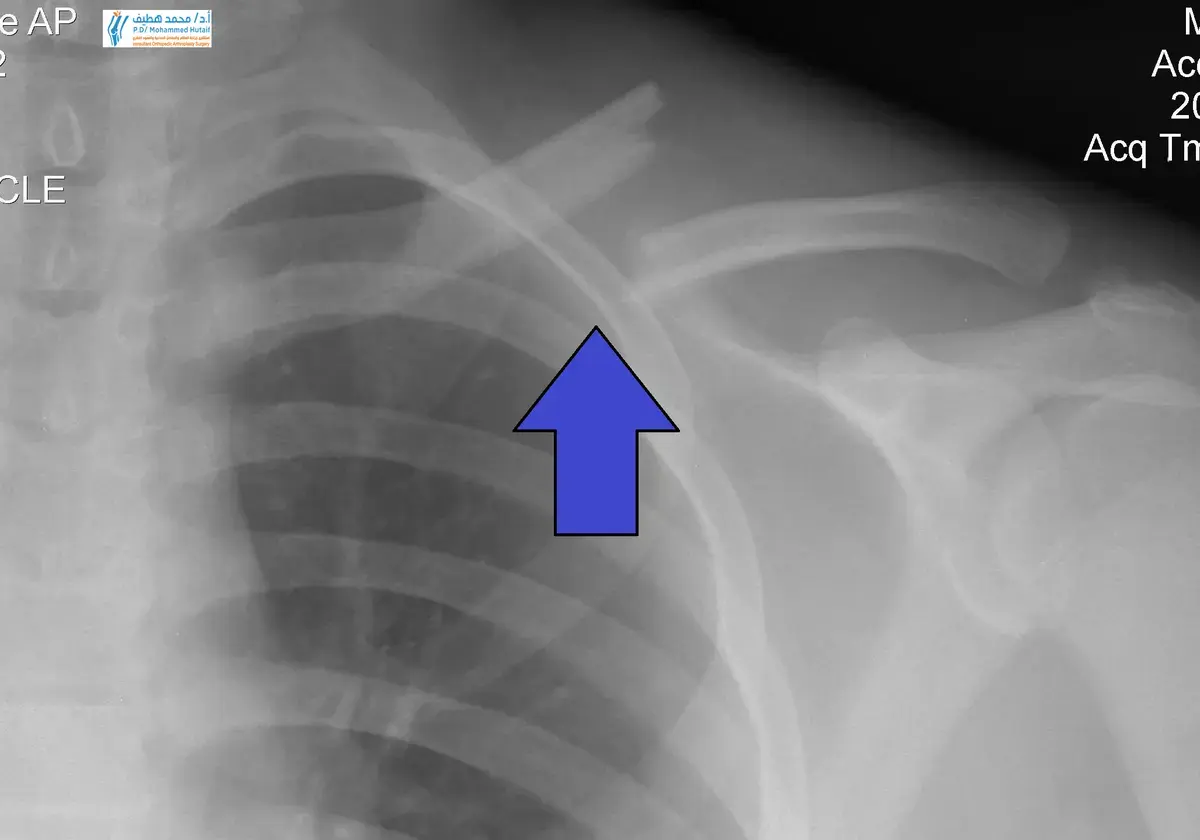

• الأشعة السينية (X-rays): هي الفحص الأولي والأكثر شيوعًا. تُظهر الأشعة السينية بوضوح موقع الكسر، نوعه، درجة الإزاحة، وعدد قطع العظم المكسورة. غالبًا ما يتم أخذ عدة صور من زوايا مختلفة (AP view, 45-degree cephalic tilt view) للحصول على رؤية شاملة.

اكتشف أحدث التوصيات الطبية الخاصة بموضوع كسر الترقوة: الأعراض، الأسباب، وكيفية علاج هذا الكسر بفعالية.، هو إصابة شائعة تتمثل في كسر العظم الطويل الذي يربط القص بلوح الكتف. يحدث غالبًا بعد السقوط على الذراع الممدودة أو الكتف أو تلقي ضربة مباشرة. تشمل الأعراض الألم والتورم وانتفاخ الموضع. يُشخص بالأشعة السينية، ويُعالج معظمها بالوشاح، بينما تحتاج بعض الحالات للجراحة.